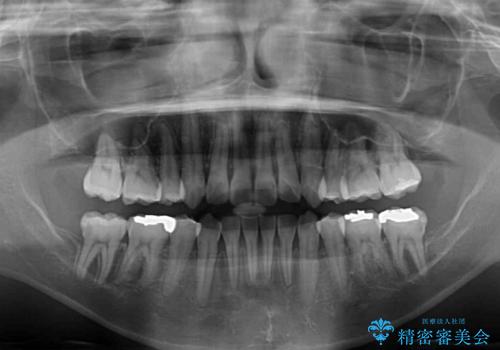

ハーフリンガルでの矯正治療は、表側矯正よりも期間がかかることが多く、抜歯矯正では3年以上かかることも珍しくありません。

デコボコが強い一方で出っ歯ではなかったため、抜歯したスペースを容易に閉じることができ、短期間での治療となりました。